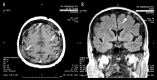

BACKGROUND Meningeal carcinomatosis is a rare complication in breast cancer patients. At present, there are no defined guidelines for its management. The efficacy of systemic treatment seems to depend on its ability to cross the blood-brain-barrier and its interaction with tumor vasculature. Metronomic chemotherapy is a known modality of drug administration able to inhibit tumor angiogenesis. CASE REPORT We present a case of symptomatic leptomeningeal carcinomatosis from breast cancer successfully treated with capecitabine. Based on the hypothesis that angiogenesis contributes to neoplastic meningitis, the patient was treated with a metronomic schedule that provided long-term clinical benefit with a very low toxicity profile. CONCLUSIONS To assess the real impact of metronomic chemotherapy in patients with meninges involvement, a phase II study will be starting soon in our institution. A review of the literature concerning the management of meningeal carcinomatosis is also presented.